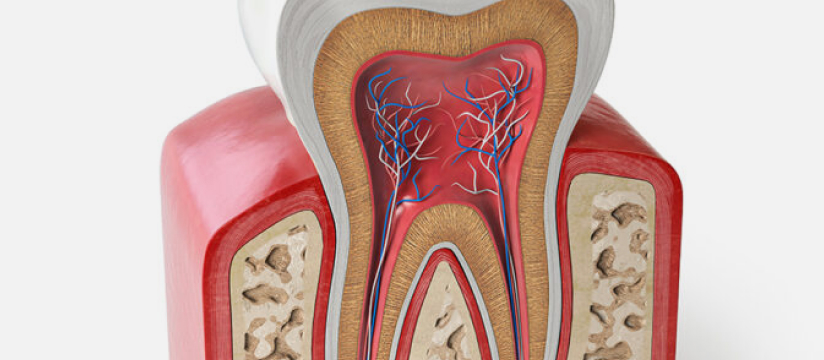

Пульпит - это заболевание, при котором воспаляется нервно-сосудистый пучок (пульпа). Пациенты часто называют болезнь воспалением нерва.

Соединительную ткань зуба защищает дентин. При своевременном лечении кариеса пульпа остается герметичной из-за твердой оболочки (дентина и эмали). При развитии кариозного поражения целостность костной ткани нарушается, микроорганизмы попадают на мягкую часть, вызывая воспаление.